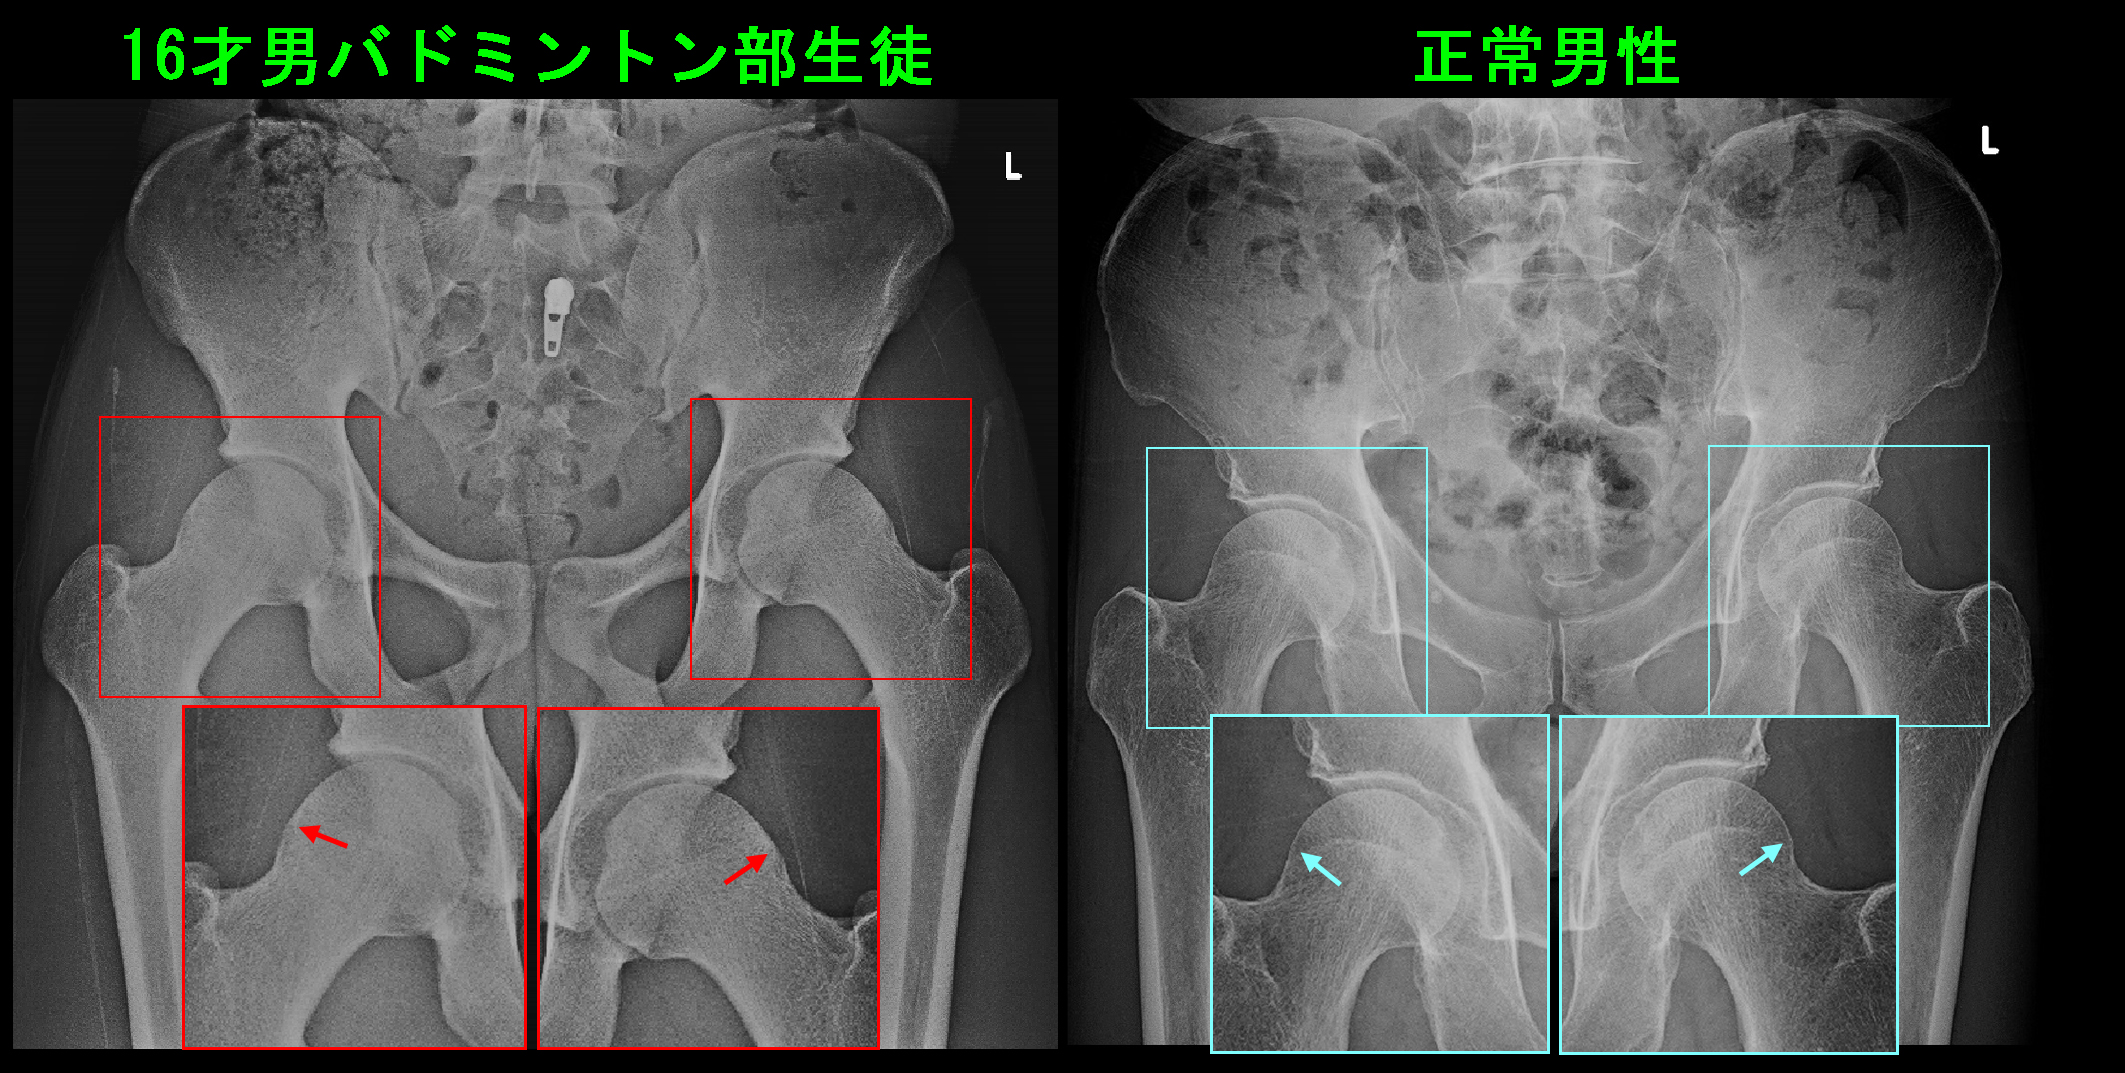

16才男Xp1.jpgS君の場合、レントゲン像で軽微なのですが、異常が確認されます。整形外科でFAIと呼ばれる所見です。FAIとはfemoral acetabular impingementの略で、日本語では大腿骨寛骨臼インピンジメント(インピンジメント=衝突)となります。右側の側面像では赤矢印の部分で大腿骨の骨頭部がわずかに肥厚しています。

16才男Xp3.jpgS君の股関節レ線像と正常男性の股関節レ線像を比較すると、微妙ですが大腿骨頭部の外側部分が少し盛り上がっています。これがFAIの原因となります。大腿骨骨頭の外側部が盛り上がっていると、股関節を屈曲していった時にその膨隆部が臼蓋の周囲の関節唇を圧迫して損傷することになるのです。